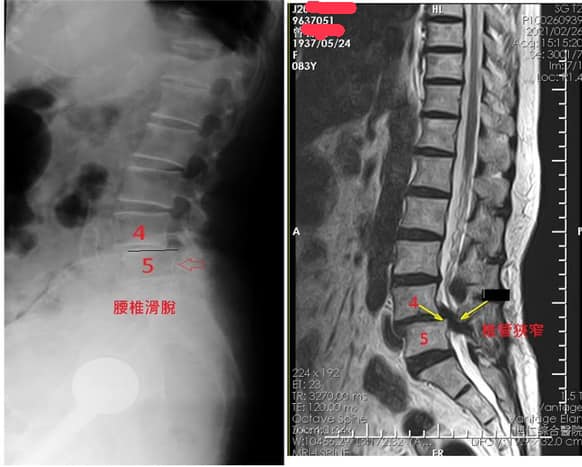

Cervical Spine Treatment Cases 腰椎治療案例 #巨大椎間盤突出一定要開刀嗎? #兩家醫學中心外科醫師說很嚴重! #有沒有辦法逆轉勝... 2021.08.10 ❖ 椎間盤突出治療醫案 ❖晨起痛爆整個人無法工作心情沮喪 😂骨科醫師說復健如果沒效可... 2022.05.12 #天才年輕賽車手巨大椎間盤突出醫案 #八周治療完全逆轉勝康復 #重新回到合法賽車場競... 2021.07.20 #腰椎滑脫痛苦不堪 #右腳麻痛無法彎腰刷牙 #感謝桃園市楊小姐熱情見證 #患者親自贈送... 2021.06.15 #巨大椎間盤突出醫案 #真的逆轉勝超感動 #三個月治療完全徹底改善 #脊刻救援成功 #徹... 2021.06.12 ⭕️L4L5巨大椎間盤突出治療醫案 🌟八週之內解除危機逆轉成功 😁順利降級成功解封印 💪... 2021.07.08 #腰椎多節椎管狹窄治療醫案 #腎臟病患者可接受中醫微創筋膜療嗎? #感謝台北市信義區張... 2021.06.01 #腰椎手術失敗綜合症候群 #感謝桃園呂伯伯熱情見證 #何時必須優先考慮再次動刀 #脊刻... 2021.07.31 #感謝新店吳先生熱情見證 #車禍後導致椎間盤突出醫案 #傳統復健六周無效痛苦不堪 #脊... 2021.05.29 #椎間盤突出治療醫案 #破紀錄三週解決 #真的逆轉勝 #感謝新莊周先生熱情見證 #脊椎整... 2021.05.26 #脊椎滑脫合併椎管狹窄醫案 #感謝台北市曹阿姨熱情見證 #之前大痛到無法走路只能拐杖... 2021.05.14 #嚴重椎管狹窄醫案導致寸步難行 #最嚴重走路無法超過十公尺 #疼痛到整個人憂鬱到不... 2021.05.07 #巨大椎間盤突出醫案逆轉勝 #感謝台北士林王先生熱情見證 #脊椎整合中醫微創療法 #原... 2021.04.29 #台灣越南國際醫療成功 #脊椎整合中醫微創療法逆轉勝 #腰椎椎間盤突出醫案 #曾經大痛... 2021.04.23 #椎間盤突出逆轉勝醫案 #原本骨科建議開刀 #脊刻救援成功 #感謝雲林患者陳小姐熱情見... 2021.04.09 ← 上一頁 7 8 9 10 11 下一頁 →